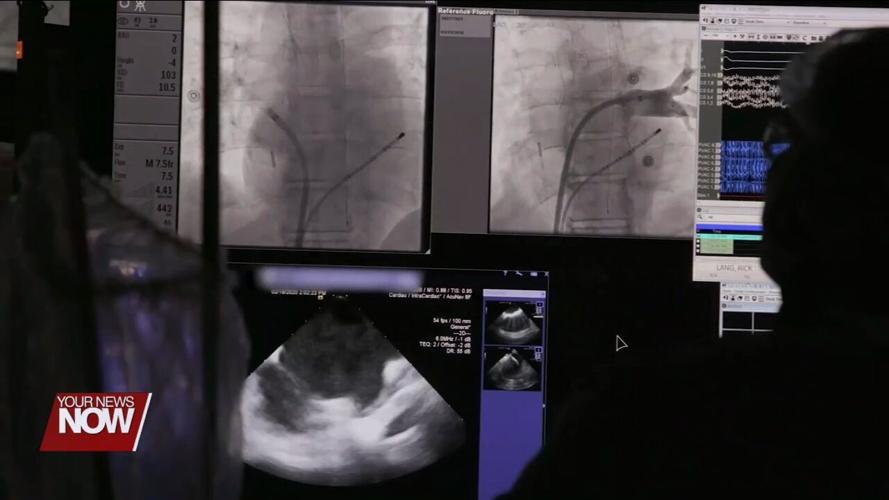

Dr. Emile Daoud at the Ohio State University Wexner Medical Center helped create a way to move the esophagus an entire inch away from the heart during treatment. The device is inserted down the patient's throat, gently shifting the esophagus left and right — moving it out of harm's way.

"By pulling in or using suction force and then moving the entire segment over to the side, you then create a safe pathway where the physician can deliver the energy to treat the atrial fibrillation," said Dr. Daoud.

A clinical trial led by Ohio State found over a third of patients had esophageal injuries after an ablation. But with the new device, less than five percent had any injury. For Amanda, that meant peace of mind going into her AFib treatment, without worry of dangerous side effects down the road.